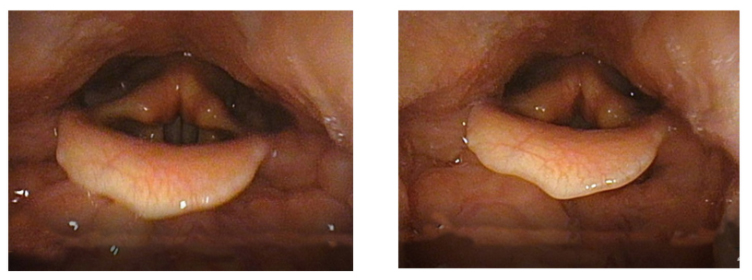

The experimental component of this research suggests that the technique of Coup de la Glotte may function better when used in conjunction with the technique of Voix Blanche. The glottis filming indicates that Coup de la Glotte tends to constrict and narrow the vocal tube. The pharynx is pressed inwards and the larynx tends to place itself in a slightly higher position.

Image 11 & 12: The filming was made by Inselspital Bern

Image 11 illustrates the onset of F5 without Coup de la Glotte. Image 12 illustrates the exact moment of onset of F5 with Coup de la Glotte. When the onset is executed whith Coup de la Glotte the pharynx muscles presses inwards, narrowing the vocal tube. The constriction even seems to push the larynx slightly upwards. It may be possible to train the larynx to stay fixed in low position when executing Coup de la Glotte, although this experiment suggests that it naturally rises. This indicates that the technique of Coup de la Glotte best suits the high larynx position, not a fixed lowered larynx which Stark and Austin claim to be Garcia’s intention.[75] The Coup de la Glotte causes a slim, narrow vocal tube. The wideness of the vocal tube affects the formants and, consequently, the timbre. Garcia claimed that the Coup de la Glotte gives stability to the tone and phrase. This narrow timbre, as illustrated in the middle of image10, was probably his vocal ideal.